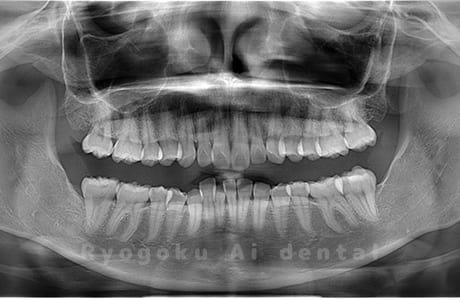

水平埋伏の親知らず

歯茎の中で完全に横に生えてしまうタイプです。

この親知らずを水平埋伏智歯と言います。このタイプはほとんどが下顎のケースです。真横に生えているので抜歯の際は難易度が高く2~3つに砕いて分けて抜歯をします。